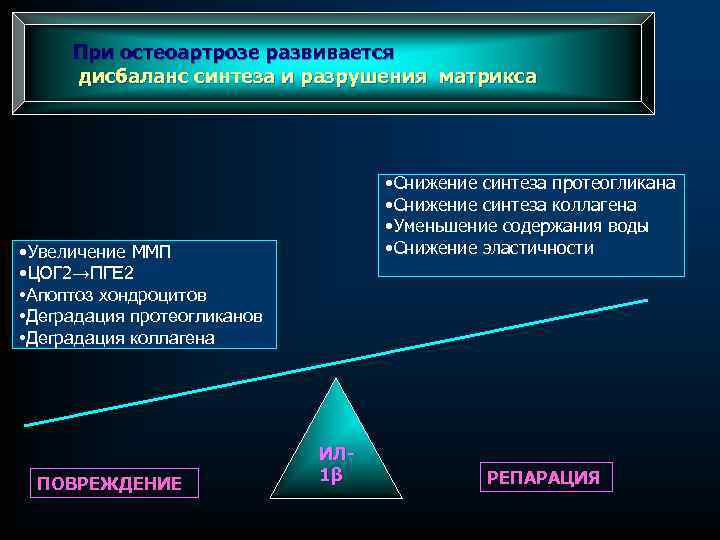

При остеоартрозе развивается дисбаланс синтеза и разрушения матрикса • Снижение синтеза протеогликана • Снижение синтеза коллагена • Уменьшение содержания воды • Снижение эластичности • Увеличение ММП • ЦОГ 2→ПГЕ 2 • Апоптоз хондроцитов • Деградация протеогликанов • Деградация коллагена ПОВРЕЖДЕНИЕ ИЛ 1β РЕПАРАЦИЯ

При остеоартрозе развивается дисбаланс синтеза и разрушения матрикса • Снижение синтеза протеогликана • Снижение синтеза коллагена • Уменьшение содержания воды • Снижение эластичности • Увеличение ММП • ЦОГ 2→ПГЕ 2 • Апоптоз хондроцитов • Деградация протеогликанов • Деградация коллагена ПОВРЕЖДЕНИЕ ИЛ 1β РЕПАРАЦИЯ